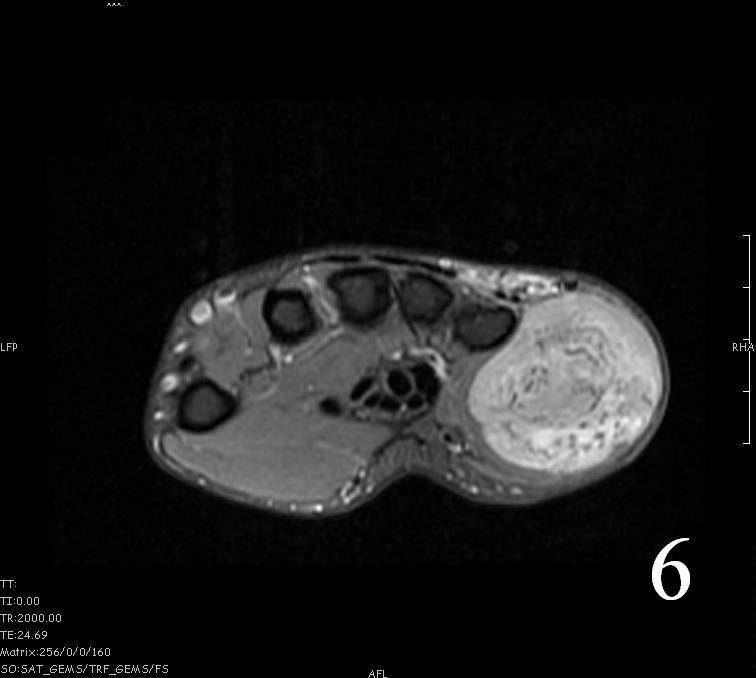

- Hyperintense signal on T2, sometimes low to intermediate signal on T2 if there is extensive fibrous tissue within the tumor (Fig. 6, Fig. 9).

Fig. 4-9: MRI of a rhabdomyosarcoma of the hand. The MRI is nonspecific and shows a heterogeneous mass particularly on postgadolinium images T1 W images (Fig. 8) and T2 W images (Fig. 9).